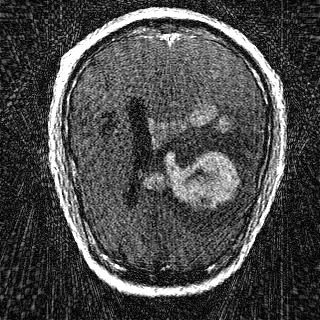

This article presents a novel undersampled magnetic resonance imaging (MRI) technique that leverages the concept of Neural Radiance Field (NeRF). With radial undersampling, the corresponding imaging problem can be reformulated into an image modeling task from sparse-view rendered data; therefore, a high dimensional MR image is obtainable from undersampled $k$-space data by taking advantage of implicit neural representation. A multi-layer perceptron, which is designed to output an image intensity from a spatial coordinate, learns the MR physics-driven rendering relation between given measurement data and desired image. Effective undersampling strategies for high-quality neural representation are investigated. The proposed method serves two benefits: (i) The learning is based fully on single undersampled $k$-space data, not a bunch of measured data and target image sets. It can be used potentially for diagnostic MR imaging, such as fetal MRI, where data acquisition is relatively rare or limited against diversity of clinical images while undersampled reconstruction is highly demanded. (ii) A reconstructed MR image is a scan-specific representation highly adaptive to the given $k$-space measurement. Numerous experiments validate the feasibility and capability of the proposed approach.